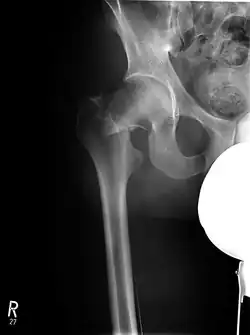

Laterale Schenkelhalsfraktur mit Adduktions-Dislokation -

Im Vergleich dazu ein gesundes Hüftgelenk